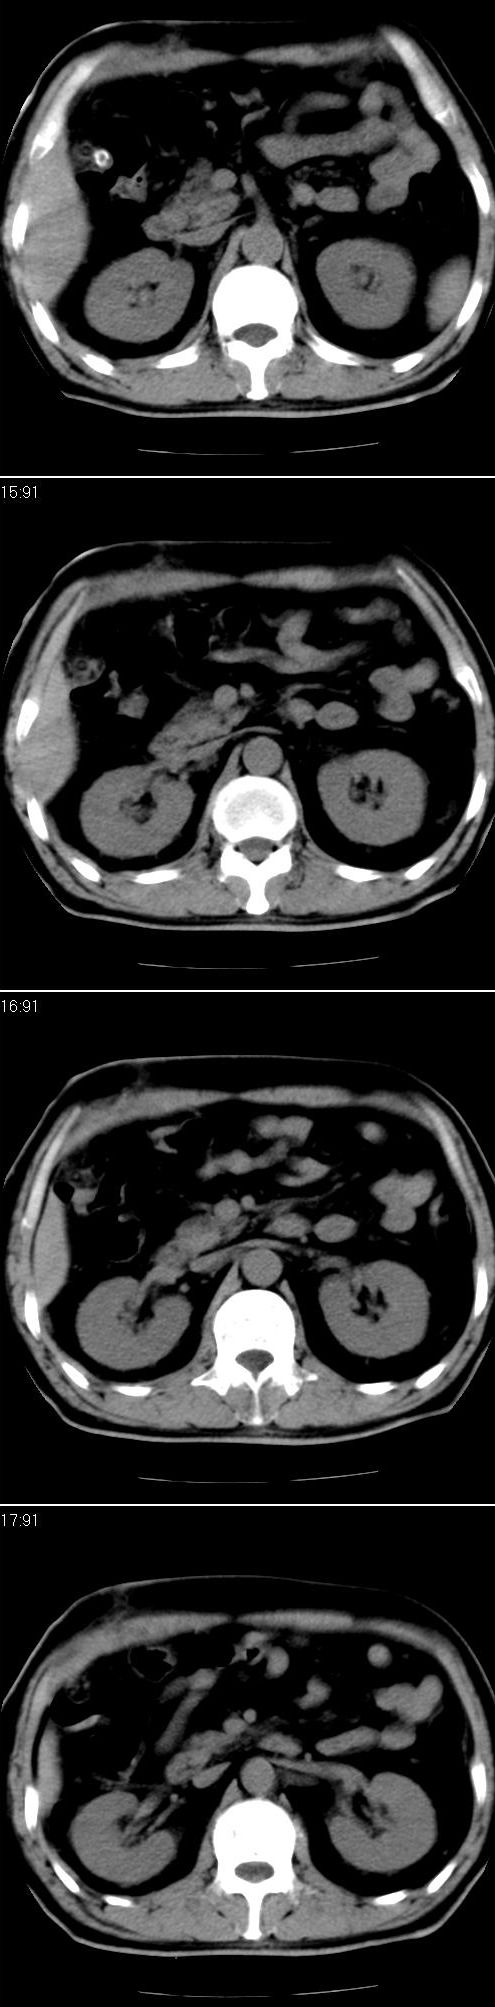

男,57岁。因胆结石阻塞性黄疸入院。这是胆囊切除术后的照片,看看此片到底有什么问题。

肝内外胆管轻度扩张,胆囊窝内见引流管考虑胆囊切除术后改变.胃窦部软组织似增厚,建议胃镜检查.

在手术切除胆囊的过程中,发现肝门部胆总管恶性占位,因为家属不同意手术,没有切除,能看出来么?

现有资料很难说,薄层可能清楚些,如临床不提供,易诊断为术后改变。

支持 肝内外胆管轻度扩张,胆囊窝内见引流管考虑胆囊切除术后改变.胃窦部软组织似增厚,建议胃镜检查.

肝内外胆管轻度扩张。楼主提示左右肝管合汇区域壁稍厚。胆总管末段壁似也稍厚有轻度强化。就现有资料诊断难。